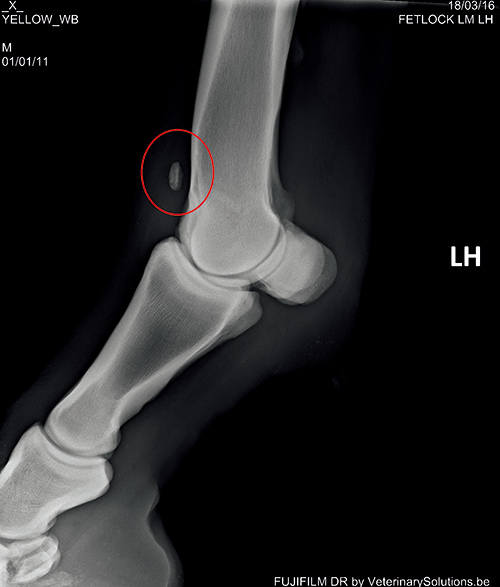

診斷和治療臨床獸醫(yī)可以通過臨床癥狀作出初步診斷。確診需要做 X 線片檢查。

例如上圖中紅圈內(nèi)是一塊很明顯的游離于球節(jié)的骨軟骨碎片??梢圆捎藐P節(jié)鏡做進一步檢查,以確定關節(jié)的損傷程度,并通過微創(chuàng)手術去除軟骨碎片,如上圖。在國外,馬主通常會在馬匹三、四歲的時候請獸醫(yī)做一次全面的 X 線片檢查來評估它們的關節(jié),一旦發(fā)現(xiàn) OCD,及早進行手術能最大程度減少其對關節(jié)的損傷,保住馬兒未來的運動生命。